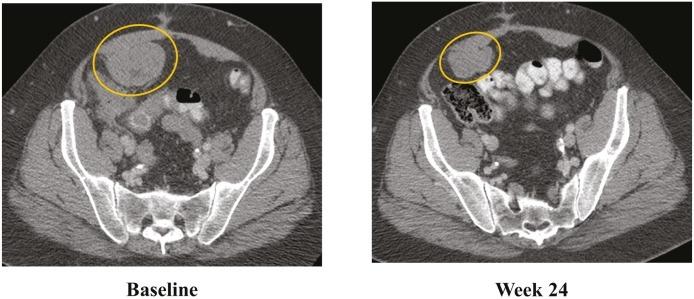

Activating oncogenic mutations of BRAF have been described in patients with gastrointestinal stromal tumor (GIST), but treatment of GIST with BRAF inhibitors and mechanisms of mediating the emergence of resistance in GIST have not been reported. Dabrafenib is a potent ATP-competitive inhibitor of BRAF kinase and is highly selective for mutant BRAF in kinase panel screening, cell lines, and xenografts. We report prolonged antitumor activity in the first patient with V600E BRAF-mutated GIST who was treated with a BRAF inhibitor. Whole exome sequencing performed in tumor tissue obtained at the time of progressive disease demonstrated a somatic gain-of-function PIK3CA mutation (H1047R) as well as a CDKN2A aberration, which may have contributed to eventual resistance to treatment.

胃肠道间质瘤(GIST)患者中已发现BRAF的致癌激活突变,但BRAF抑制剂治疗GIST及其介导GIST耐药出现的机制尚未见报道。达拉非尼是一种有效的BRAF激酶ATP竞争性抑制剂,在激酶组筛选、细胞系和异种移植中对突变型BRAF具有高度选择性。我们报告了首例接受BRAF抑制剂治疗的V600E BRAF突变型GIST患者的长期抗肿瘤活性。在疾病进展时获取的肿瘤组织中进行的全外显子测序显示存在体细胞功能获得性PIK3CA突变(H1047R)以及CDKN2A异常,这可能导致了最终的治疗耐药。